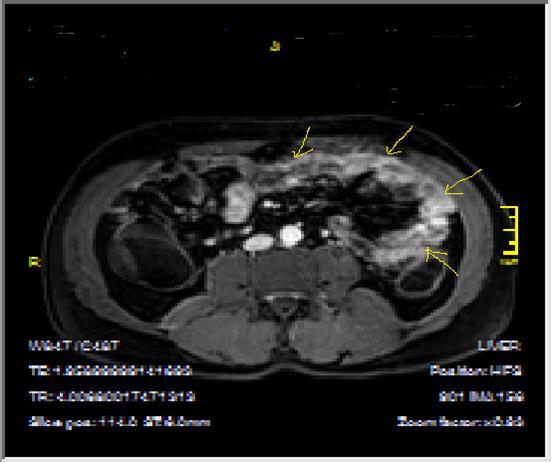

Bowel wall thickening with increased luminal and extra-luminal signal changes on FS images, showing active inflammation, edema in the adjacent intraperitoneal and mesenteric spaces, active inflammation; bowel wall thickening and enhancement on post-contrast T1W images plus high signal intensity on T2W- FS images7, 9, 12, 14, 17, 18, 19, 20, 21 (Figure 4a-b).

Figure 4a.Mucosal involvement and lack of opacified ileal segments with loss of intestinal folds and increased bowel wall thickness due to Crohn’s disease on T2W coronal sequence after OCA, presented at 37 years old male with moderate Crohn’s disease.

Figure 4b.Mucosal, luminal and bowel wall involvement in Crohn’s disease with skipped lesions, seen at T2W axial image after OCA, presented at 45 years old male with severe inflammatory disease.